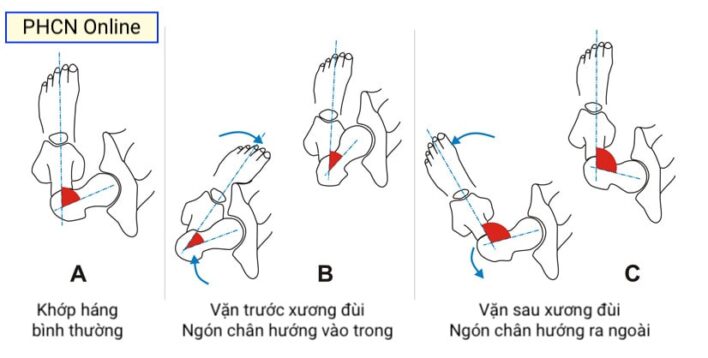

Các biến dạng xoay của chi dưới ở trẻ đang lớn tương đối thường gặp, làm cho các bậc phụ huynh lo lắng và có thể là nguyên nhân của đau khớp háng, gối và cổ chân sau này. Biến dạng xoay thường được bố mẹ hoặc người chăm sóc của trẻ phát hiện khi thấy trẻ đi với ngón chân đưa vào trong (in-toeing) – thường gặp nhất và được trình bày chi tiết trong bài viết này, hoặc đưa ra ngoài (out-toeing).

Nguyên nhân và tiến triển

Ngón chân xoay vào trong thường là do một trong ba loại biến dạng: bàn chân khép (MTA), xoắn vặn vào trong của xương chày và vặn ra trước quá mức của (chỏm) xương đùi. Nguyên nhân thay đổi theo lứa tuổi của trẻ. Trong một hai năm đầu thường là do bàn chân khép (đơn độc hoặc kèm với xoắn vặn xương chày vào trong). Ở tuổi nhà trẻ, nguyên nhân thường là xoắn vặn vào trong xương chày (đơn độc hoặc kèm với bàn chân khép) và có thể một hoặc hai bên. Ở tuổi nhi đồng, nguyên nhân thường là tăng vặn trước của xương đùi, hầu như là hai bên và đối xứng.

Xoay ở háng (đùi) thường được đánh giá với bệnh nhi ở tư thế nằm sấp, háng duỗi và gối gập đến 90°. Đánh giá tầm xoay trong và xoay ngoài của khớp háng. Gia tăng xoay trong khớp háng biểu hiện vặn trước của xương đùi, ngược lại tăng xoay ngoài có thể là biểu hiện của vặn sau và đụng chạm xương đùi – ổ cối. Để xác định mức vặn ra trước của xương đùi có thể đánh giá test Craig: đo góc giữa xương chày và trục đứng dọc vuông góc với mặt giường. Góc này ở người bình thường khoảng 15 độ.

Vặn trước xương đùi

Bình thường có một thay đổi rất lớn của góc vặn trước này trong quá trình phát triển: góc trung bình lúc mới sinh là 40 °, và giảm xuống còn khoảng 14–18 ° khi trưởng thành. (Nữ thường có góc vặn trước lớn hơn nam).

Trong trường hợp vô căn, biểu hiện lâm sàng thường gặp nhất là trẻ đi với ngón chân vào trong (góc tiến bàn chân âm) và xương bánh chè “lác” trong, hay vấp ngã và ngồi với tư thế “chữ W” (hai gối gập và cẳng chân dang ra phía sau. Khám lâm sàng phát hiện góc tiến bàn chân vào trong, tăng xoay trong khớp háng, giảm xoay ngoài, tăng vặn trước xương đùi. Tăng vặn trước xương đùi thường được chẩn đoán sau ba tuổi, cao điểm vào khoảng 4-6 tuổi, và sau đó giảm dần. Tình trạng này thường tự chỉnh khi trẻ lớn lên đến tuổi trưởng thành (>80%), và thái độ xử trí là trấn an gia đình và theo dõi. Thông thường, can thiệp phẫu thuật không được xem xét trước khi trẻ đạt 9–10 tuổi.